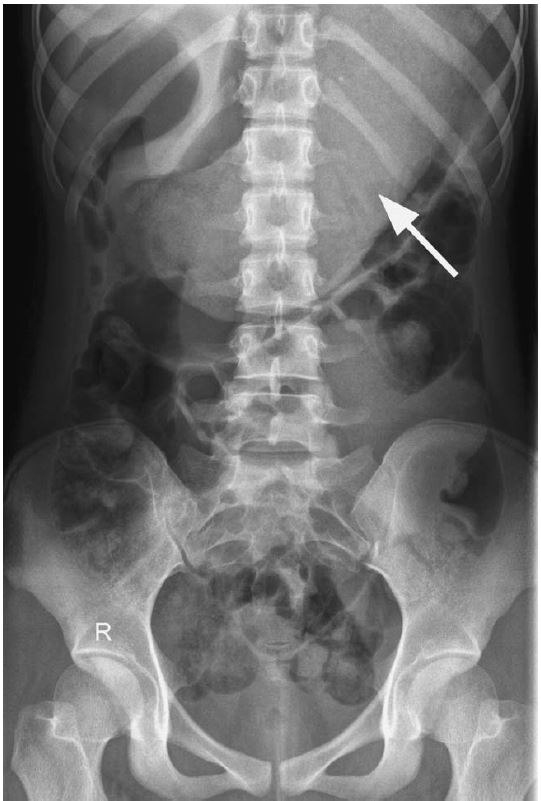

From radiopaedia.org

Image How Are Bezoars Removed A bezoar forms when certain substances or materials accumulate and clump together in the gi tract, creating a solid mass. During endoscopy, doctors sometimes use forceps, a laser, or other instruments to break bezoars into pieces so that they can pass through or be. Endoscopic removal is indicated for patients who have bezoars that fail to dissolve, moderate to severe. How Are Bezoars Removed.

Gastric bezoar Image How Are Bezoars Removed The exact process of bezoar formation can vary depending on the. A bezoar is an undigested mass of material in the digestive tract that may produce symptoms. Endoscopic removal is indicated for patients who have bezoars that fail to dissolve, moderate to severe symptoms due to large bezoars, or both. A bezoar forms when certain substances or materials accumulate and. How Are Bezoars Removed.